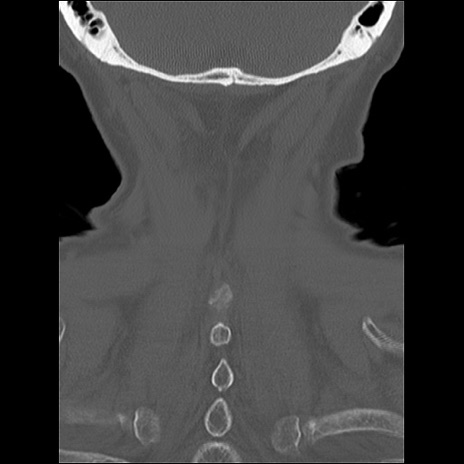

症例48 頚椎CT(冠状断像)

頚椎CT